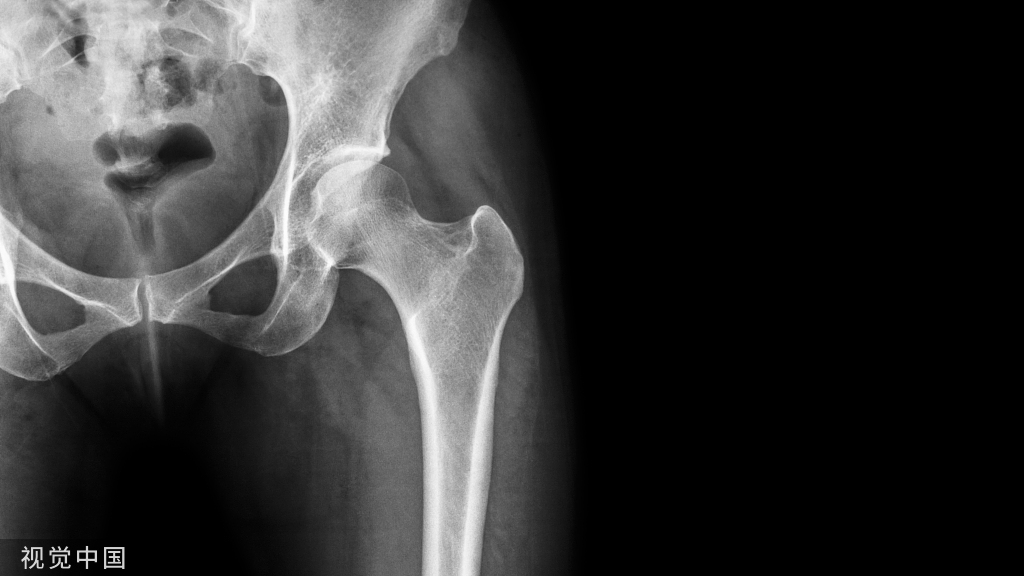

不同类型髋关节置换术的视图。左上:天然髋关节。上中、右:半关节置换术需要用人工植入物替换原有股骨头和股颈,同时不触及原有的髋臼软骨。单极半关节置换术和双极半关节置换术的区别在于球体内是否存在额外的关节。下中:THA包括用人工假体替代股骨和髋臼表面。注意,在半关节置换术中髋臼软骨保持完整,但在全髋关节置换术中,髋臼软骨被移除。右下:在THA中,约束衬管具有锁定环,可将人工股骨头固定在适当位置,同时仍允许旋转。左下:髋关节表面置换术中,仅置换髋臼和股骨头关节面。